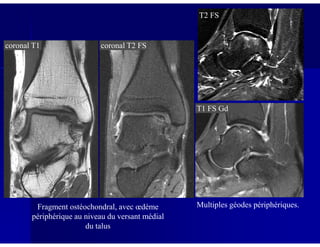

Ostéochondrite disséquante du talus

Petite niche au niveau du versant supéro-médial du dome du talus

coronal T1 coronal T2 FS

T2 FS

T1 FS Gd

Fragment ostéochondral, avec œdème

périphérique au niveau du versant médial

du talus

Multiples géodes périphériques.

Arthroscanner: niche ostéochondrale, associée à une petite ulcération du

cartilage, bien individualisée sur les reconstructions coronale et sagittale